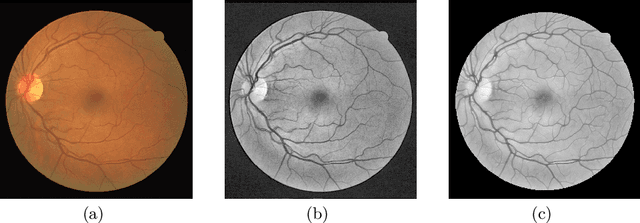

Abstract:Fundus photography and Optical Coherence Tomography Angiography (OCT-A) are two commonly used modalities in ophthalmic imaging. With the development of deep learning algorithms, fundus image processing, especially retinal vessel segmentation, has been extensively studied. Built upon the known operator theory, interpretable deep network pipelines with well-defined modules have been constructed on fundus images. In this work, we firstly train a modularized network pipeline for the task of retinal vessel segmentation on the fundus database DRIVE. The pretrained preprocessing module from the pipeline is then directly transferred onto OCT-A data for image quality enhancement without further fine-tuning. Output images show that the preprocessing net can balance the contrast, suppress noise and thereby produce vessel trees with improved connectivity in both image modalities. The visual impression is confirmed by an observer study with five OCT-A experts. Statistics of the grades by the experts indicate that the transferred module improves both the image quality and the diagnostic quality. Our work provides an example that modules within network pipelines that are built upon the known operator theory facilitate cross-modality reuse without additional training or transfer learning.